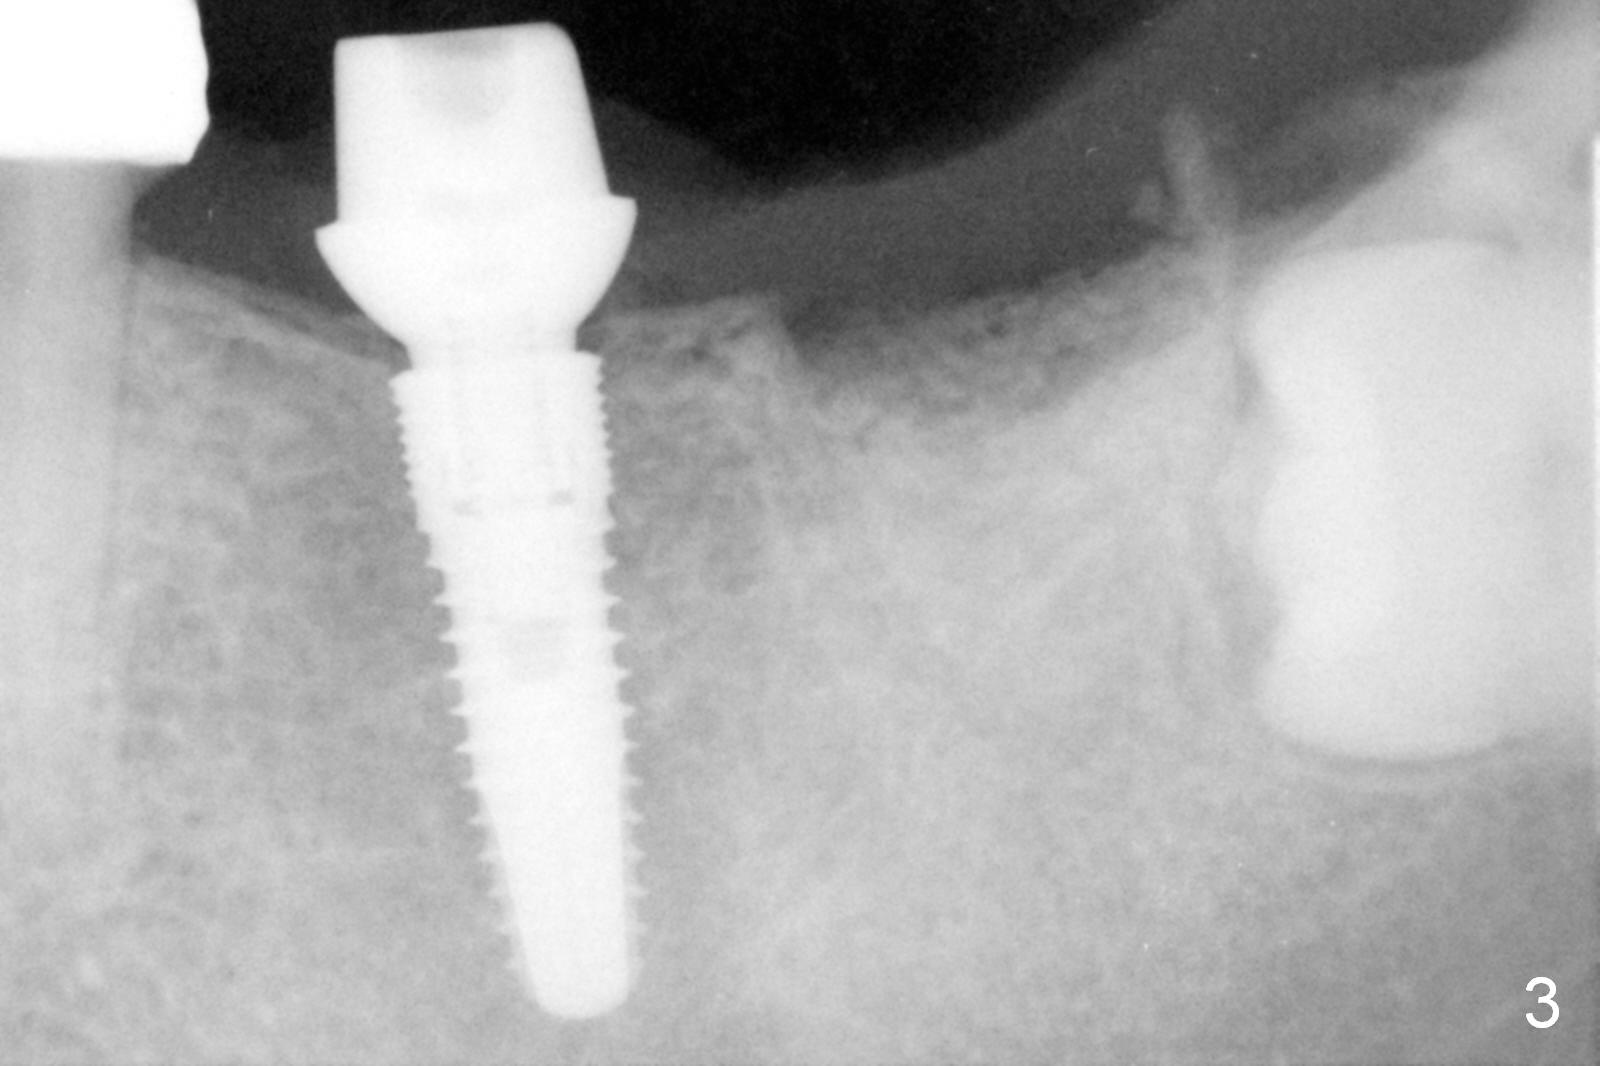

Infiltration anesthesia is enough for initial osteotomy at the site of #19 (Fig.1), but not for sectioning the tooth #18.  Block anesthesia has to be administered.  Fortunately it is safe to start osteotomy at #18 (~ 3 mm beyond the socket bottom, Fig.1 (red dashed line: the superior border of the Inferior Alveolar Canal (IAC))).  A 4.5x14 mm implant is stable at #19, while a 5x12 mm one at #18 is not (Fig.2).  Unfortunately bone graft has been placed.  When the implant is removed, a 4.5x14 mm drill is used to deepen the osteotomy for 2 mm.  The patient reports mild discomfort later on.  Hemorrhage occurs, which is stopped when the same implant is re-placed.  There is no stability.  The implant is removed (Fig.3,4).  More bone graft is placed, followed by collagen plug.  It appears that bone graft has been pushed into the IAC (Fig.4 arrowheads). Medro dose pak is prescribed.  In fact, no paresthesia is reported postop.